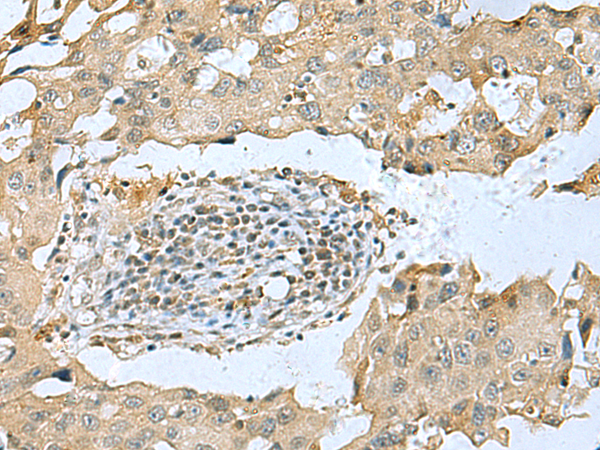

IHC positive control: |

Human tonsil and Human breast cancer |

IHC Recommend dilution: |

25-50 |